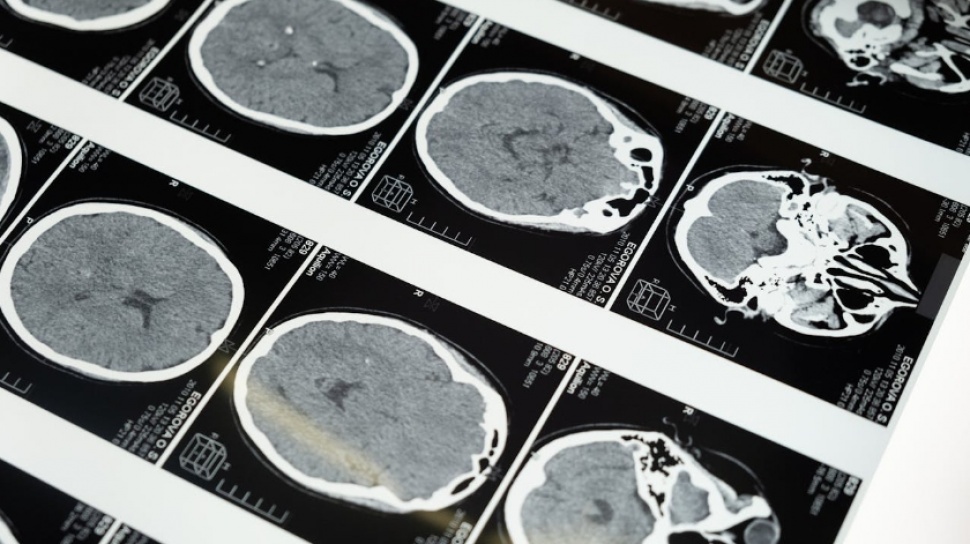

Sebuah studi baru menunjukkan bahwa otak manusia melewati lima fase perkembangan utama yang dipisahkan oleh titik balik penting. Penelitian ini melibatkan hampir 4.000 pemindaian otak dari berbagai kelompok usia, mulai dari bayi baru lahir hingga orang berusia 90 tahun. Temuan ini dipublikasikan dalam jurnal Nature Communications dan mengungkapkan bahwa aspek perkembangan otak tidak bersifat linear seperti yang selama ini diasumsikan.

Di bawah pimpinan Dr. Alexa Mousley dari University of Cambridge, peneliti mengeksplorasi bagaimana struktur otak berubah sepanjang hidup. Mereka mengidentifikasi empat titik perubahan signifikan yang terjadi pada usia 9, 32, 66, dan 83 tahun. Tahapan ini menunjukkan bagaimana otak berkaitan erat dengan berbagai kondisi neurologis dan kesehatan mental.